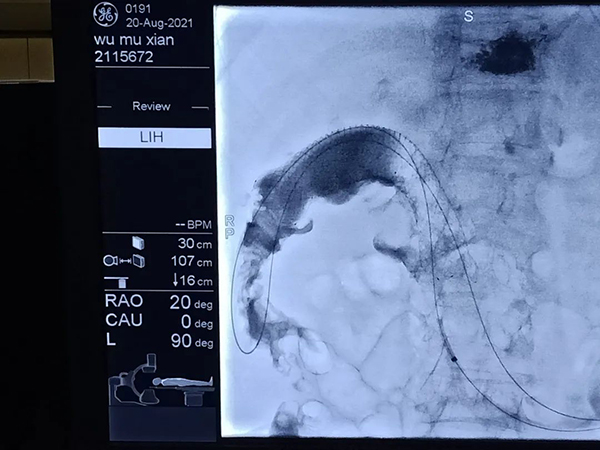

8月20日,錦州市中心醫(yī)院消化二科與介入科通力協(xié)作,為一位結(jié)腸癌腸梗阻患者實施內(nèi)鏡下結(jié)腸肝曲支架置入術(shù),成功免除患者腸造瘺的風(fēng)險,為結(jié)腸癌所致腸梗阻患者提供了再通生命之道。

由于老人年事已高,且基礎(chǔ)疾病較多,狀態(tài)差,手術(shù)機會渺茫,且家屬不同意腸道手術(shù)治療。盡快解除患者因腸道梗阻所致的痛苦是當(dāng)務(wù)之急。經(jīng)科室病例討論,消化二科主任孫軍及介入科韓洪武主任為患者量身制定了治療方案,在X線下(DSA)經(jīng)腸鏡引導(dǎo)行支架置入治療。

腸鏡檢查過程中,患者腸道內(nèi)充滿大量糞便,視野差,醫(yī)護(hù)人員反復(fù)沖洗腸道、清理腔道,醫(yī)護(hù)人員密切觀察患者狀態(tài),調(diào)整控制操作進(jìn)程,最終成功完成檢查治療。

術(shù)后患者腹痛、腹脹即刻得到緩解,進(jìn)流食后,第二日順利排出糞便。經(jīng)過醫(yī)護(hù)人員的精心護(hù)理和飲食指導(dǎo)以及家屬的悉心照料,患者進(jìn)食和體質(zhì)得到了明顯的改善,生活質(zhì)量得到了提升。